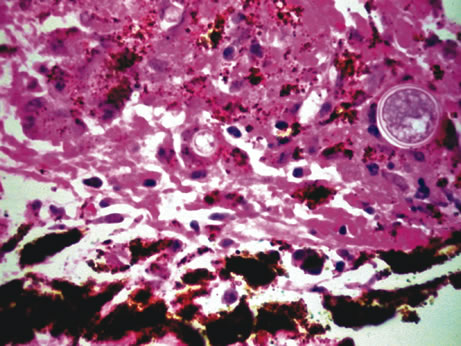

Retinochoroiditis

Necrotizing retinitis with secondary choroiditis is seen in protozoal infections such as toxoplasmosis or in herpetic infections. Infection with Toxoplasma gondii leads to retinitis and secondary choroiditis (Fig. 25), usually granulomatous.127 Congenital infection can be acquired in utero by transplacental transmission of the parasite from the infected mother to the fetus.128 Acquired disease occurs after ingestion of oocysts or tissue cysts.129–132 The congenital form of infection leads to atypical macular colobomas. Reactivation of the infection is caused by release of organisms that have remained dormant in the margins of old congenital retinal scars.133 The slowly proliferating form of the organism, termed the bradyzoite, can be seen in cysts. The rapidly multiplying form, termed the tachyzoite, may be difficult to identify in an infected retina or in immunocompetent individuals, but they are frequently seen in the retinitis of immunocompromised hosts.134 Active infection usually causes focal retinal opacification and an intense vitritis. These findings may give the appearance of a “headlight in a fog” in an immunocompetent person. In contrast, this clinical presentation is rare in patients with AIDS, in whom diffuse retinitis is observed with non-granulomatous choroiditis.134

Fig. 25. Toxoplasma retinochoroiditis. Necrotic retina shows cysts of toxoplasma gondii, and the choroid reveals granulomatous inflammation. (Hemotoxylin-eosin ×65.) Inset (Gomori methenamine silver ×160) shows cysts of the organisms.